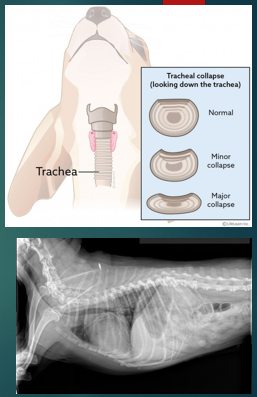

Tracheal collapse

Flattening of the tracheal rings

Commonly seen in toy/miniature breeds

Most common clinical signs is a cough - ‘goose-honk’ ‘seal-bark’

Can be elicited with pulls on lead

What is tracheal collapse?

Where cartilage tracheal rings weaken and collapse, which causes breathing difficulties, this can vary in severity